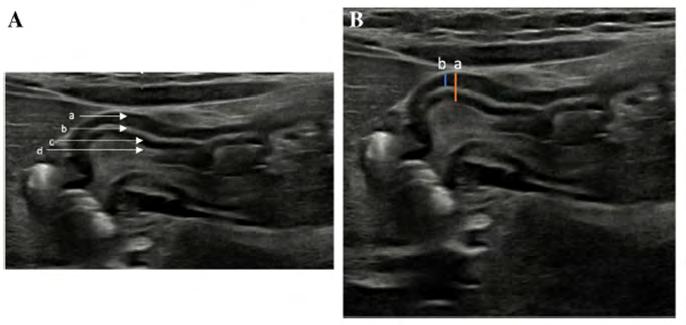

With ethics approval, the PACS system was used to search for patients who had an ultrasound for a differential diagnosis of HSP. Data was collected over a two-year period (Jan 2019 – Dec 2020). Studies with a longitudinal image using a linear transducer of 12–18 MHz were included in the analysis. Any poor quality studies were excluded. Measurements were taken off the longitudinal views as they found this plane to be the most reliable.

• Two paediatric radiologists independently measured the transverse muscle thickness of the pylorus.

• Measurement (a) includes the outer layer of muscularis propria until the inner layer of muscularis mucosa, including the hyperechoic stripe (submucosa).

• Measurement (b) includes only the muscularis propria without the submucosa and muscularis mucosa.

(Fig. 1)

Fig. 1 Normal sonographic appearance of the wall of the pylorus using a linear-array transducer, 18 MHz, in a 6-week-old female who presented with vomiting. In these transverse images of the upper abdomen, the normal pylorus is shown in longitudinal view. A Image shows the normal layers of the pylorus. (a) Hypoechoic muscularis propria; (b) Hyperechoic stripe of submucosa; (c) Hypoechoic muscularis mucosa; (d) Hyperechoic stripe of interface between mucosa and intraluminal echogenic contents.

B Image shows two different methods of measurement of the thickness of the pylorus. (a) Measurement from the outer surface of the hypoechoic muscularis propria down to the hyperechoic interface between the mucosa and intraluminal content; (b) Measurement from the outer surface of the hypoechoic muscularis propria down to the level of the outer surface of the hyperechoic stripe of the submucosa.